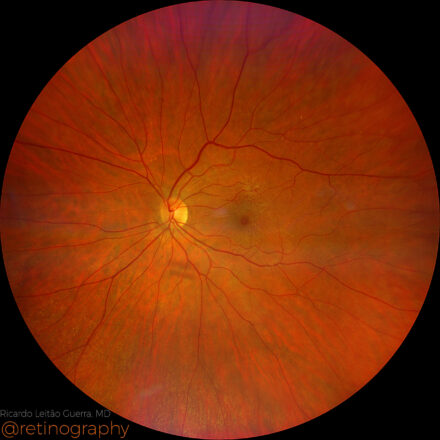

Central serous chorioretinopathy

42yo

42yo